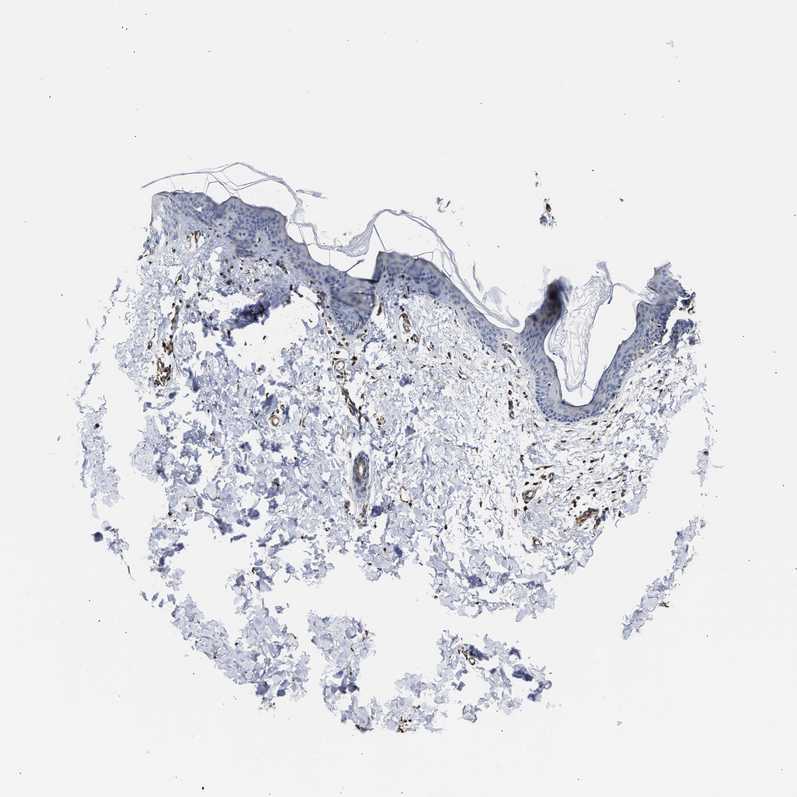

SKIN 1 - Antibody stainingi

Antibody staining in the annotated cell types in the current human tissue is reported as not detected, low, medium, or high, based on conventional immunohistochemistry profiling in selected tissues. This score is based on the combination of the staining intensity and fraction of stained cells.

Each image is clickable and will lead to virtual microscopy that enables deeper exploration of all samples and also displays staining intensity scores, fraction scores and subcellular localization as well as patient and tissue information for each sample.

Antibody HPA020357

Langerhans Not detected

Fibroblasts Medium

Keratinocytes Not detected

Melanocytes Not detected

SKIN 2 - Antibody stainingi

Epidermal cells Low